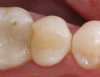

Replacement of existing restorations is responsible for 75% of all operative dentistry.15,19 The reasons for placement and replacement of restorations of direct restorative materials include: primary caries (Figure 1 and Figure 2); recurrent caries (Figure 3); poor margins (Figure 4 and Figure 5); restoration fracture (Figure 6 and Figure 7); tooth fracture (Figure 8); esthetics (Figure 9); non-carious tooth structure lost (attrition, abrasion, abfraction, erosion) (Figure 10); and pain/sensitivity.

Fig. 3 Maxillary first molar with mesiobuccal tooth fracture and recurrent caries.

Figure 3  Maxillary first molar with mesiobuccal tooth fracture and recurrent caries.

Figure 3